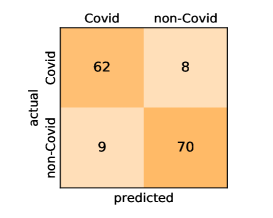

Here, we present and discuss the obtained results for detecting COVID-19 on the considered CT image datasets with different deep networks. We report the quantitative results along with the confusion matrices for every single architecture of the adopted networks.

On the SARS-CoV-2 CT dataset, ResNet101 achieves the best overall performance with respect to almost all evaluation metrics, with an average accuracy and F1-score of and , respectively. The model also achieves an average sensitivity rate of indicating that, on average, only two COVID-19 images are falsely predicted as negatives. It is also powerful enough to correctly identify all Non-COVID-19 cases with only one false positive resulting a specificity rate of . The highest sensitivity score of is achieved by the InceptionV3 model, where only one COVID-19 image is falsely predicted as negative on average. The SqueezeNet model obtains the lowest performance with respect to all evaluation metrics with a fairly acceptable average accuracy and sensitivity scores of and , respectively. Also the ShuffleNet architecture obtains satisfactory performance with approximately improvements on average for all metrics compared with SqueezeNet. Although the results obtained by these models are inferior compared with the rest of models, but they are more efficient. This matches their main objective of reducing the computational costs rather than improving their visual recognition abilities. The rest of models achieve competitive performance and very promising results with slight performance differences. Comparing the different variants of ResNet and DenseNet, we can see that the deeper variants from each architecture yield a slightly better performance. The deeper ResNet101 and ResNeXt101 show a marginal gain in performance compared with their shallower counterparts. The details about class-wise results for each model are summarized in the confusion matrices in Figure 9.

Our models achieve fairly good performance compared with the recently published work using the exact network architectures. This can bet attributed to a better optimization of our models and the effectiveness of our fine-tuning strategy using custom-sized inputs determined specifically for each architecture. Here, we see that DenseNet201 outperforms all other architectures. The model achieves average accuracy and sensitivity scores of and , respectively. It also identifies all COVID-19 images with only four images, on the average, are falsely predicted as Non-COVID-19. DenseNet169 achieves the second best average accuracy of and a very high sensitivity identical to the best model. The DenseNet121 and Xception models have nearly identical results for all evaluation metrics. We observe that small-sized networks such as ResNet18 achieves comparable results with other deeper models. The SqueezeNet and ShuffleNet models perform at a similar level of accuracy. The variants of the ResNeXt models have comparable results and perform as good as the different ResNet variants. A detailed analysis on the class-wise results for individual models is presented in the confusion matrices in Figure 10.